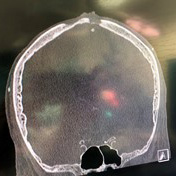

Anschließend resezierten wir ein Radiusstyloid bei Impingement nach vaskularisierter Knorpel-Knochen-Transplantation von der Patella zur Rekonstruktion einer posttraumatisch destruierten Radiusgelenkfläche. Auch in Salzburg wurden wir vom gesamten OP-Team freundlich aufgenommen. Anschließend konnten wir den beiden Mund-, Kiefer-, Gesichtschirurgen Professor Gaggl (Salzburg) und Professor Rasse (Wien) bei der Rekonstruktion der vorderen Schädelkalotte bei kraniofazialer Fehlbildung bei einem 7 Monate alten Kind zuschauen, während Dr. Bürger assistierte. Diese Operation war ein Highlight, das ich in meinem klinischen Alltag nie gesehen hätte. Am selben Abend fuhren wir wieder zurück nach Klagenfurt, während der Fahrt ließen wir die Erlebnisse revue passieren.